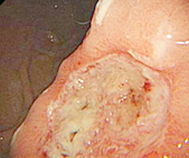

在成都博仕医院治愈的萎缩性胃炎患者